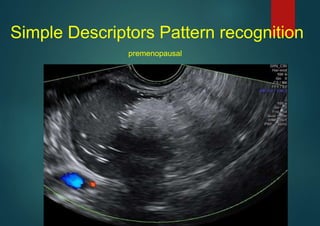

Simple Descriptors Pattern recognition

premenopausal

unilocular

,

Dermoid

mixed echoes, shadows, premenopausal